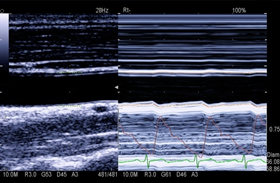

通过对实时画面的逐帧对比,极速捕捉异常信息并慢放成像,用于快速运动脏器特别是对心脏的观察,把握瞬息变化,减少漏诊和误诊。